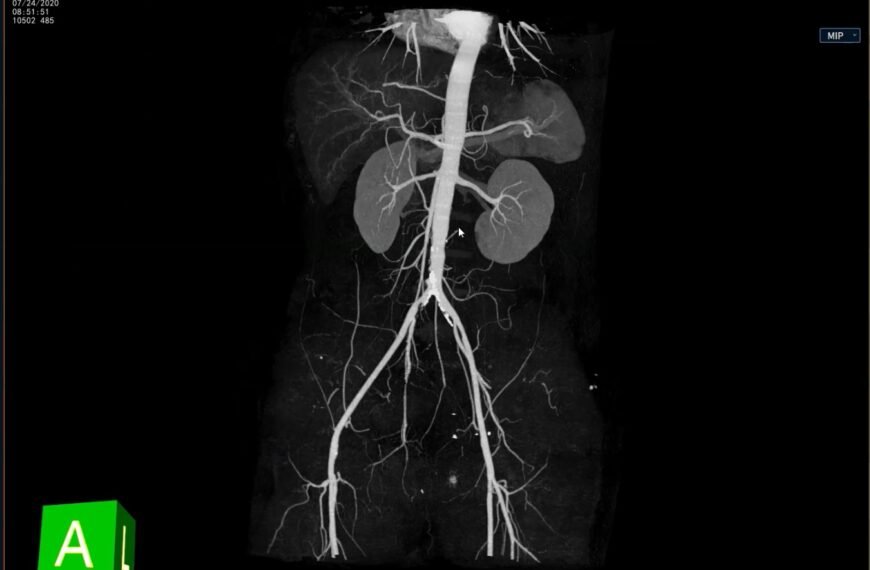

Mapeo vascular de alta precisión con IntelliAtlas

Mapeo vascular de alta precisión con IntelliAtlas Pro: flujo de trabajo optimizado con protocolo LAA LLM Radiologia Mapeo…

Mapeo vascular de alta precisión con IntelliAtlas Pro: flujo de trabajo optimizado con protocolo LAA…